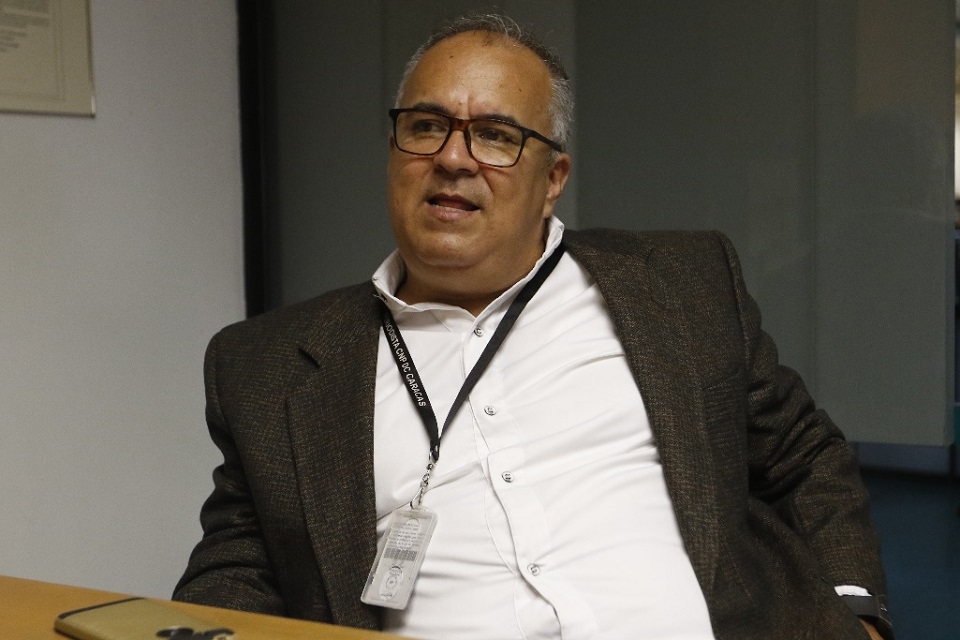

Durante el periodo de gestación, el desarrollo del cerebro tiene un rápido crecimiento que continúa en la vida posnatal durante un tiempo prolongado. Así, aumenta de tamaño cuatro veces en la etapa preescolar; sin embargo, los principales cambios estructurales se dan durante la niñez y la adolescencia, periodo en el que alcanza cerca de 90% del volumen que tendrá en la edad adulta, describe el doctor Carlos Paz Tres, jefe del Departamento de Neurofisiología del Instituto Nacional de Neurología y Neurocirugía de México, quien señala que el volumen del cerebro está limitado por el tamaño del cráneo.